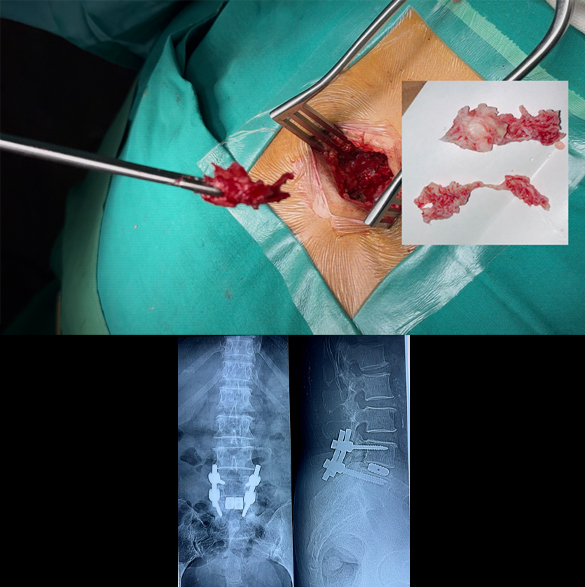

Spinal Tumors Excision

Surgical excision (removal) is generally required for all kind of spinal tumors. Most procedures for spinal tumor excision require opening up spine at the back and then removal. These procedures may require spinal instrumentation (fixation with screws and rods) in some cases. The goal is to remove as much of the tumor as possible, potentially curing some benign tumors, or to alleviate symptoms like pain and nerve compression in others. Surgical approaches vary depending on tumor type and location, and may involve techniques like en-bloc resection (removing the tumor in one piece) or more targeted removal of the tumor tissue. Complications of the surgery may includewound infection, bleeding, recurrence, and weakness or paralysis.

Spinal Disc Prolapse Surgery (Open, Micro-endoscopic & Endoscopic Surgery, TLIF/PLIF)

There are multiple surgical options for treatment of spinal disc prolapse. Commonest are Open discectomy or microdiscectomy. Other options are micro-endoscopic, and pure endoscopic. Not all patients can be treated with endoscopy; smaller unilateral disc prolapse is one of the indication. Some patients with spine alignment issues may require spinal instrumentation (fixation with screws and rods) during disc removal surgery. Similarly disc replacement surgery (TLIF/PLIF) is also an option in fully active middle age patients. Generally, the outcome of disc prolapse surgery is good and patients is mobilized on the same day while full recovery can take 2 to 4 weeks time. A few complications of the surgery may be wound infection, bleeding, postoperative muscle spasm, and nerve damage (rare and usually temporary).